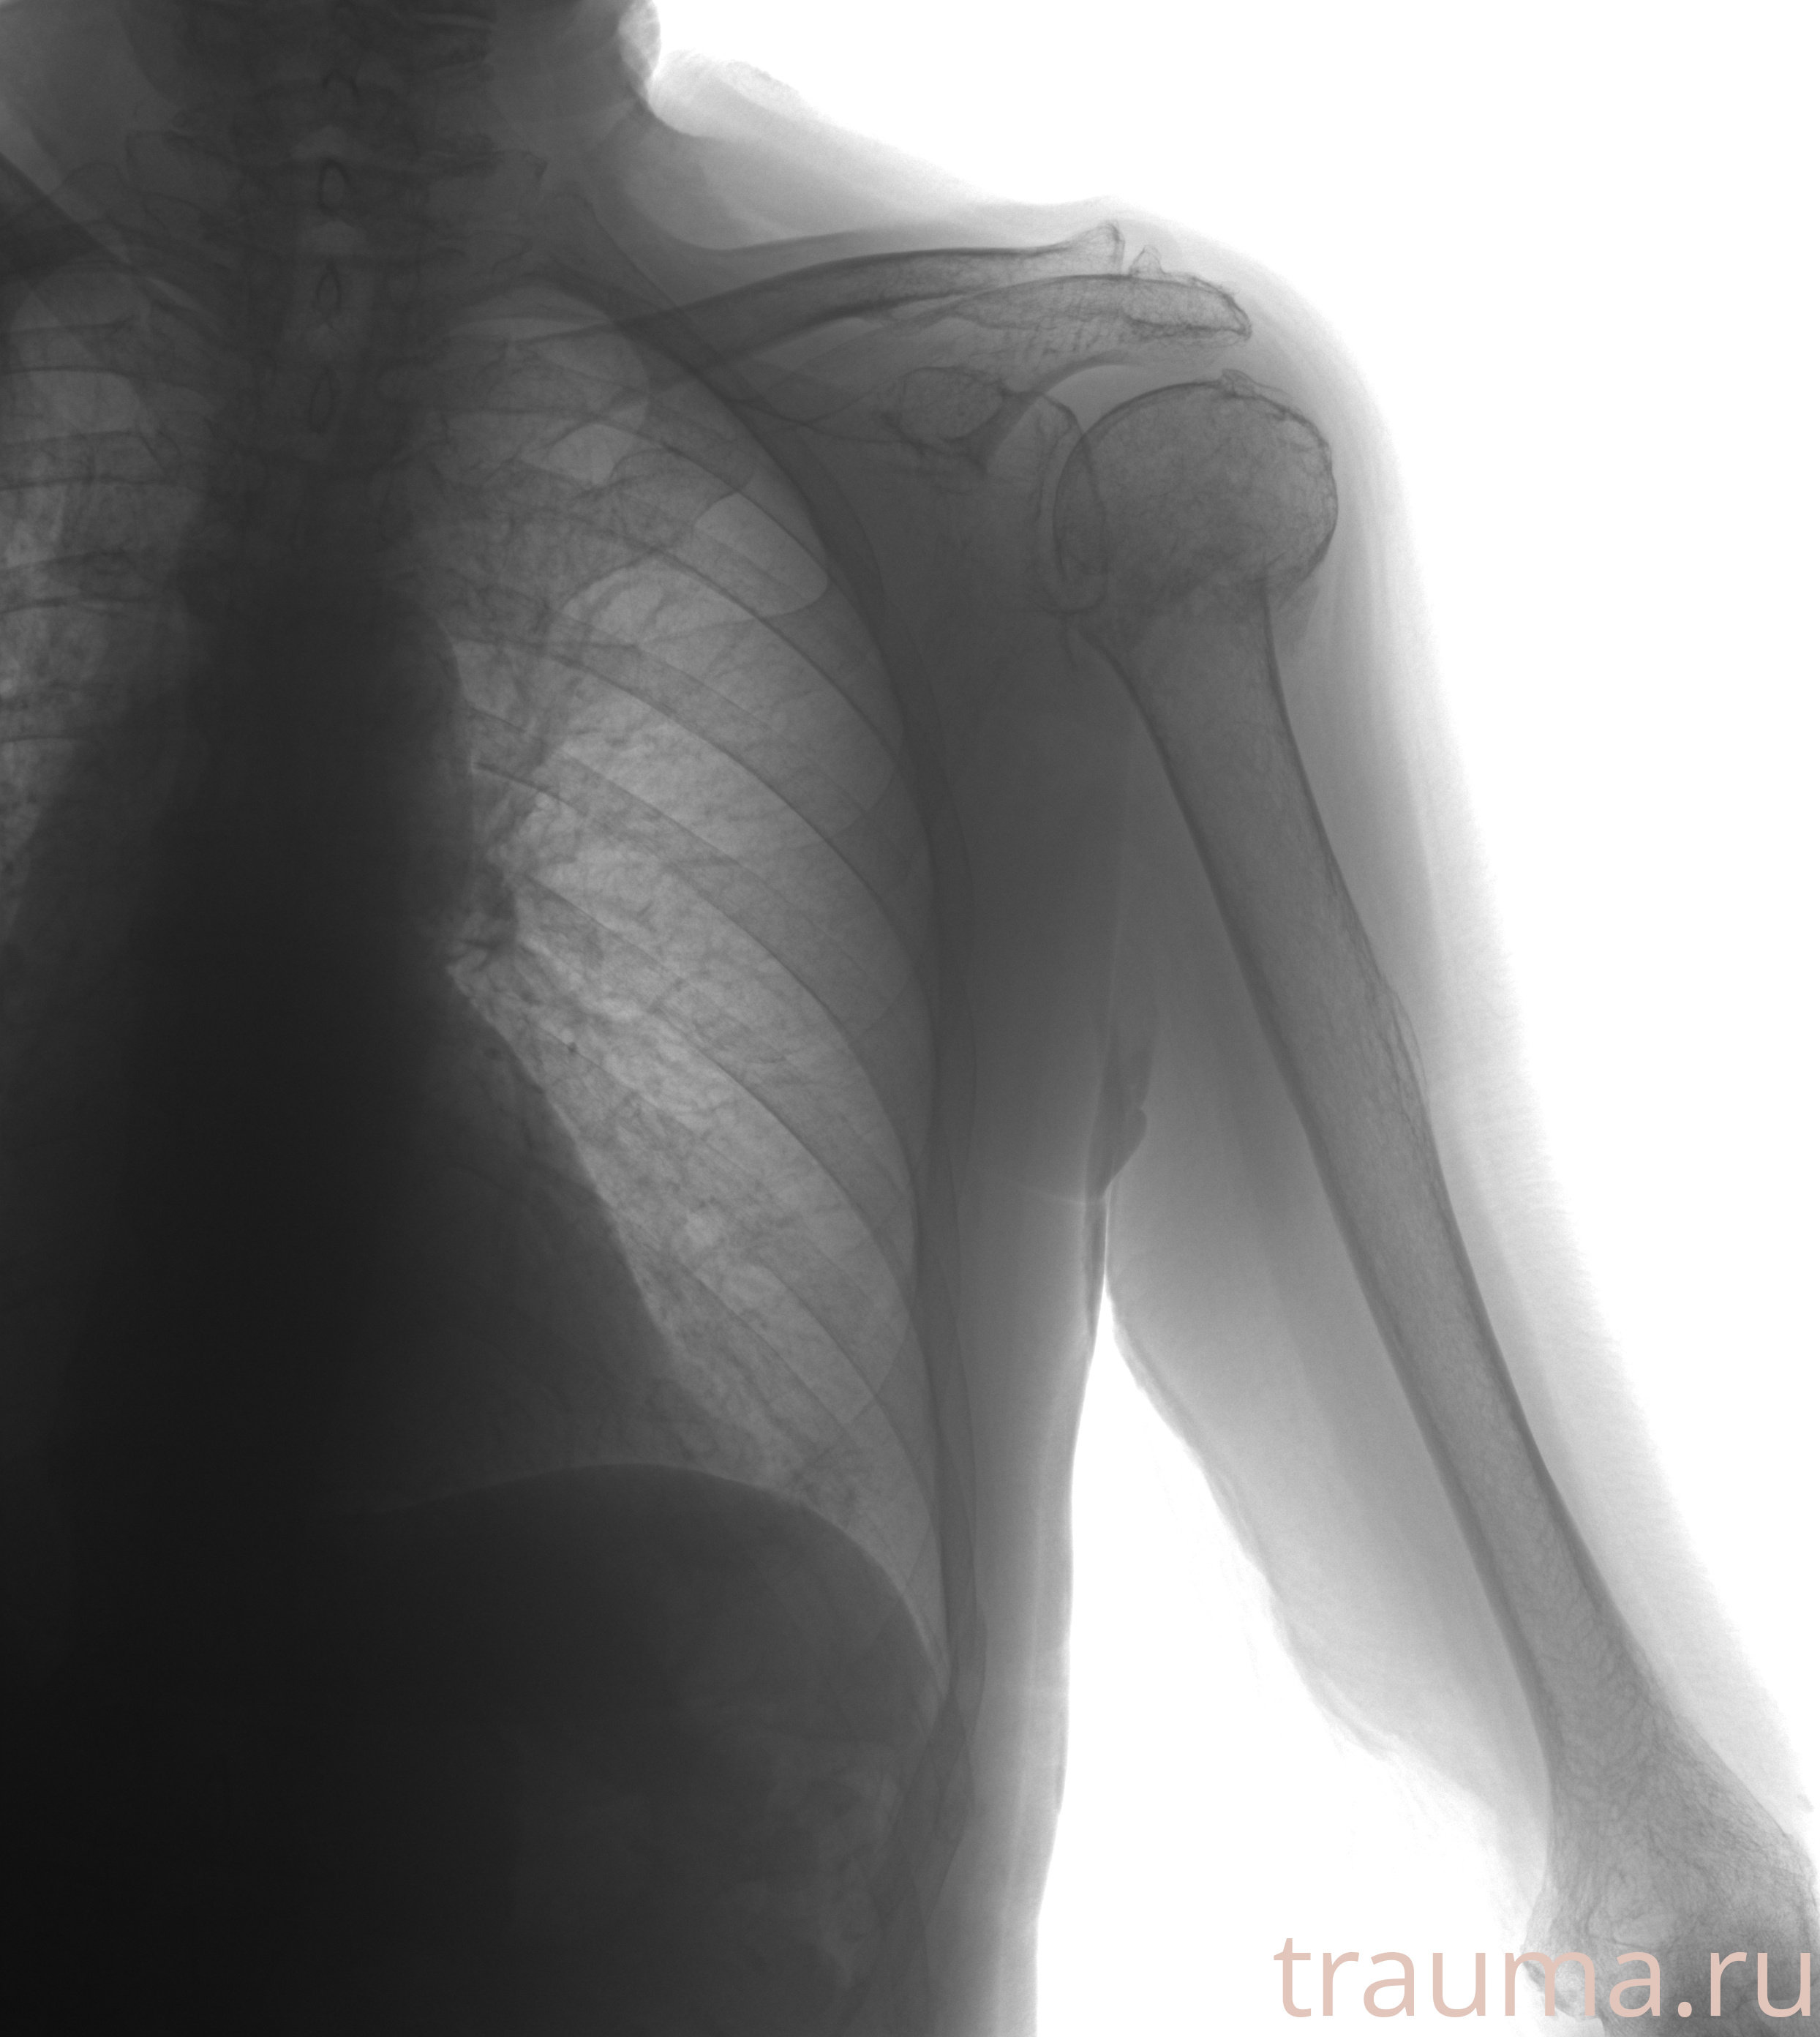

Рентгенограммы

Рентген на дому: по вашему адресу приезжает врач-рентгенолог, травматолог-ортопед с мобильным рентгеновским аппаратом, проводит диагностику травмы или заболевания, делает необходимые рентгенограммы, дает рекомендации по дальнейшему лечению. Получить качественные снимки в домашних условиях возможно благодаря уникальной методике, разработанной МосРентген Центром для института  Склифосовского